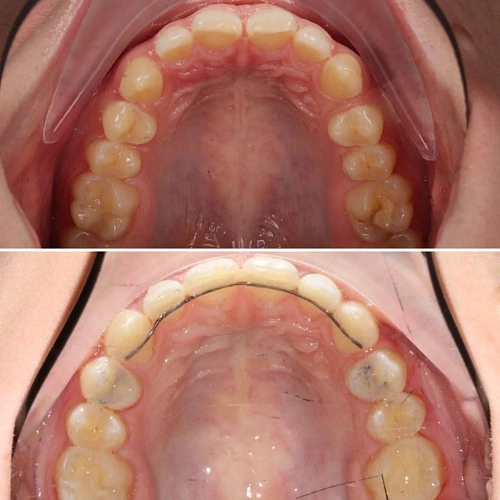

Скученность зубов, обе челюсти сужены — зубам не хватало места в ряду.

Брекет-система на обе челюсти. Расширить зубные дуги и убрать скученность. Срок — около 1,5 лет.

Зубы выровнены, скученность устранена. Установлены несъёмные ретейнеры на обе челюсти, сняты сканы для ретенционных кап. Ортопедия не требуется, рекомендовано лечение у терапевта.

Решение: Установили брекеты на обе челюсти. Расширили дуги, убрали скученность — всё за 15 месяцев. Визиты раз в 4–6 недель для замены дуг. После снятия зафиксировали ретейнеры на обе челюсти, сняли сканы для кап. Ортопед подтвердил, что протезирование не требуется. Терапевт рекомендовал лечение — пациентка записана.

Скученность на обеих челюстях при сужении дуг — классический случай. Зубы здоровые, корни в хорошем состоянии, мотивация у пациентки высокая. Всё это позволило уложиться в 15 месяцев без осложнений. Ортопед подтвердил, что протезирование не нужно. Рекомендовала пройти терапевтическое лечение для полного завершени